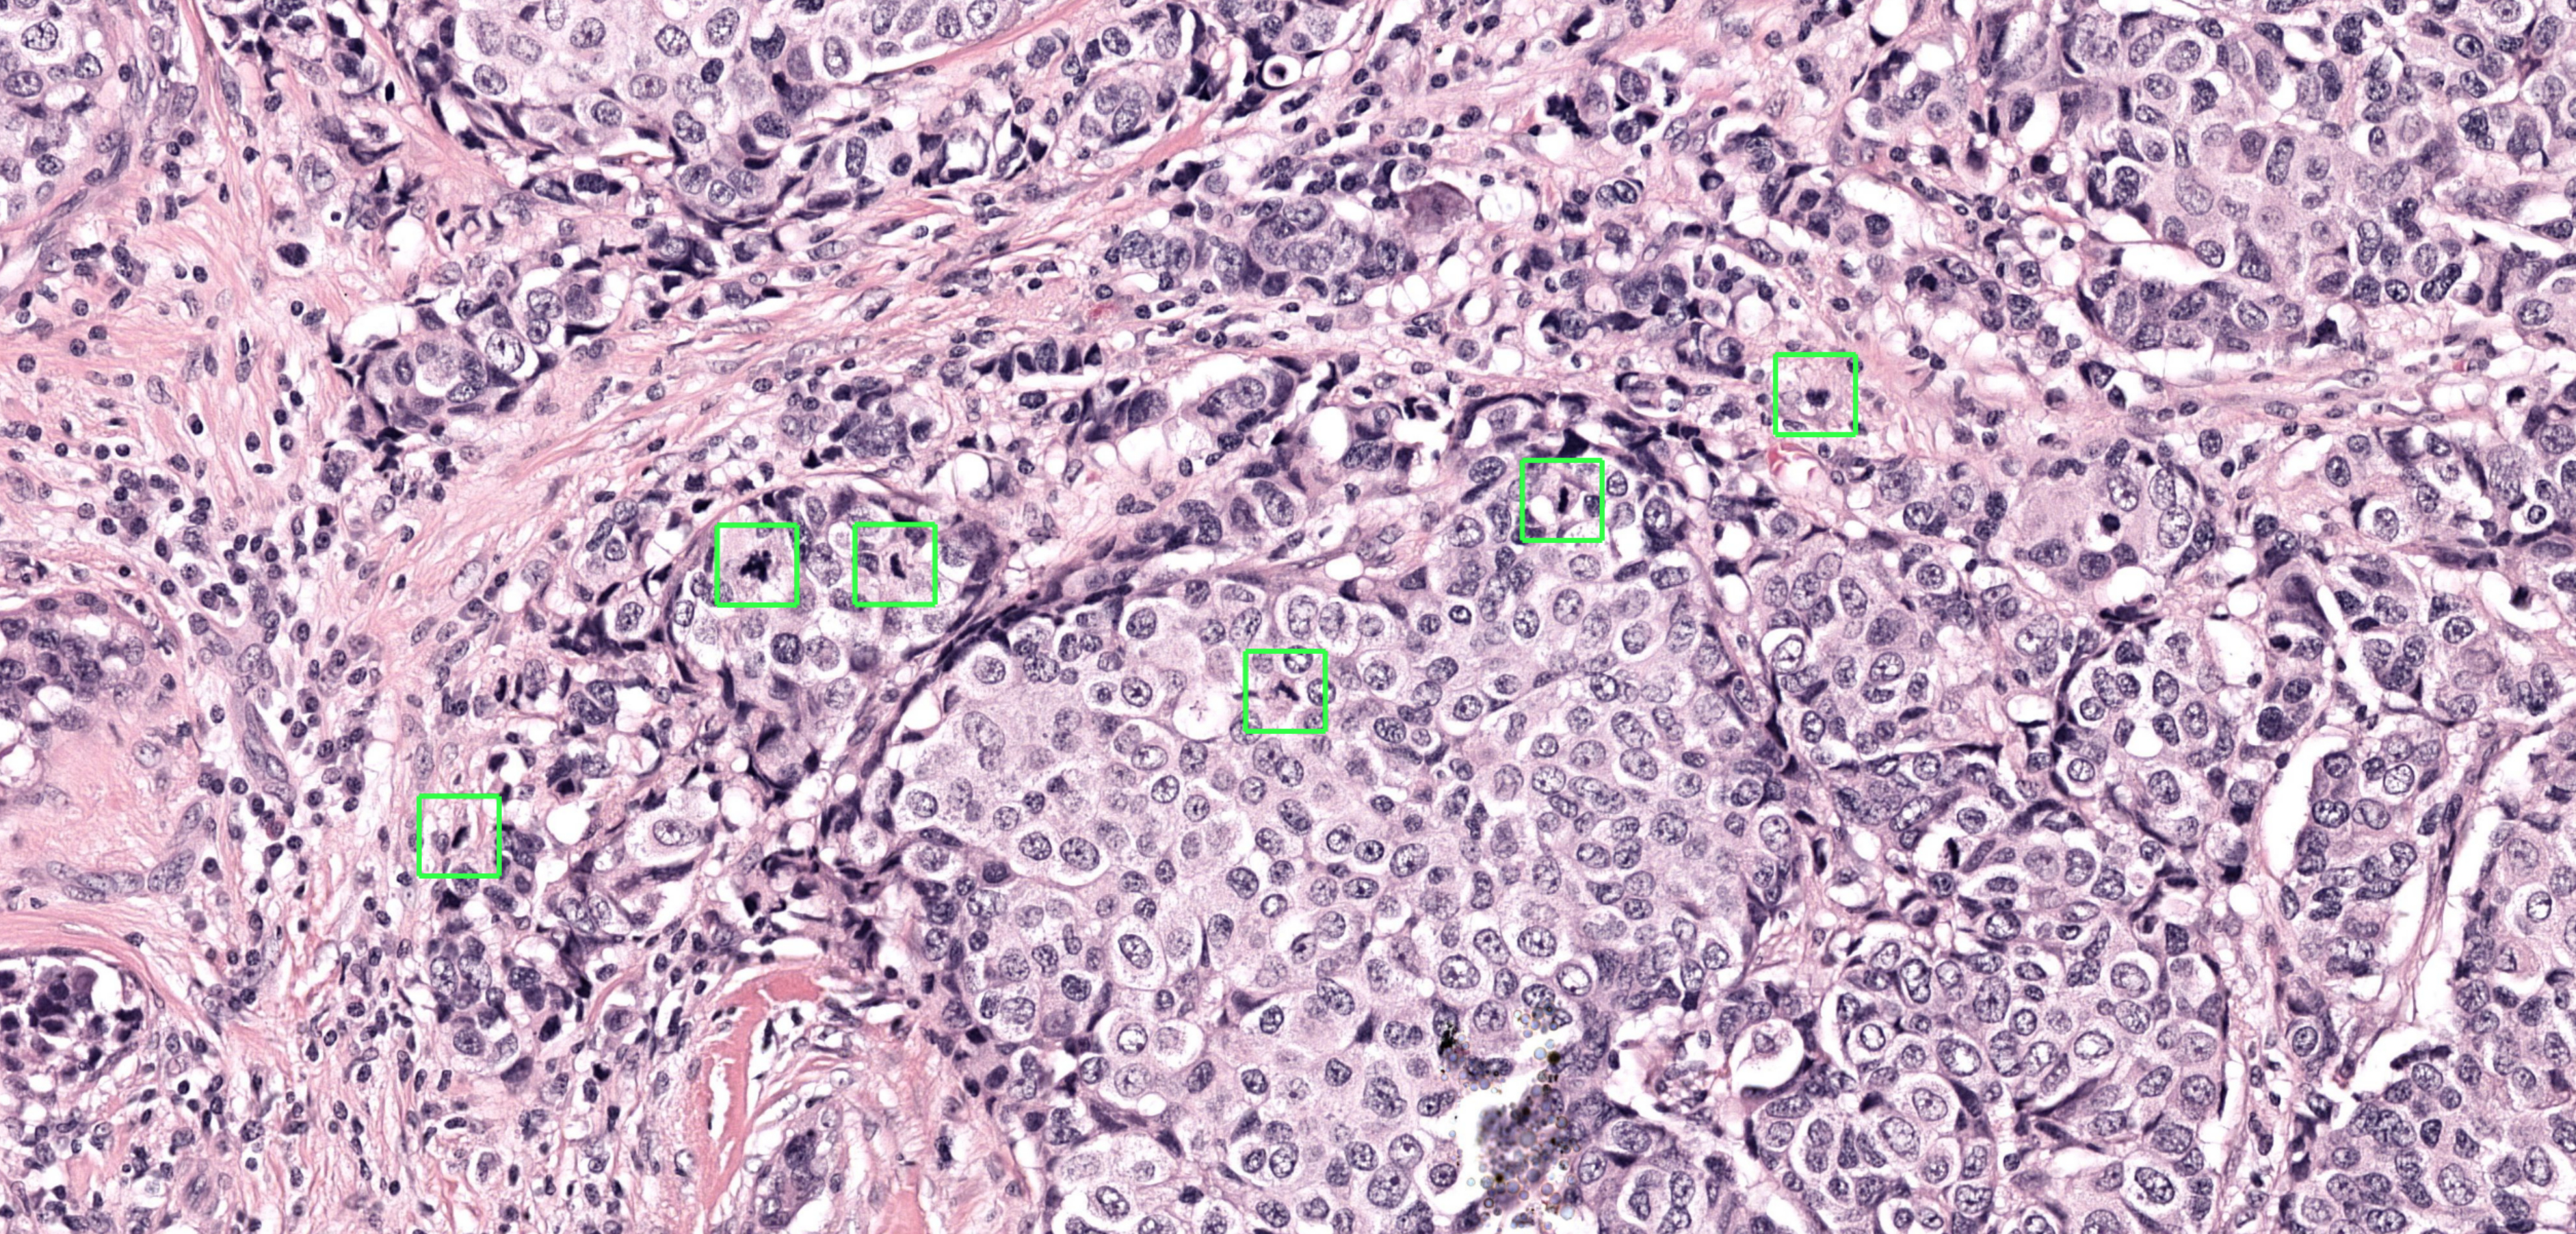

NIMEGA, Paesi Bassi--(BUSINESS WIRE)--Aiosyn, azienda di software medico specializzata nelle soluzioni per la patologia basate sull'intelligenza artificiale, ha rilasciato il suo primo algoritmo IA nella linea di prodotti Mitosis: Aiosyn Mitosis Research. Questo innovativo algoritmo di deep learning è stato progettato per effettuare automaticamente la scansione delle cellule in fase di divisione (mitosi) affiancando i laboratori di patologia di ricerca nel rilevamento della figura mitotica in immagini di vetrini interi da biopsie e resezioni oncologiche. Il secondo algoritmo della linea, Aiosyn Mitosis Breast per uso diagnostico, è attualmente in fase di convalida clinica.